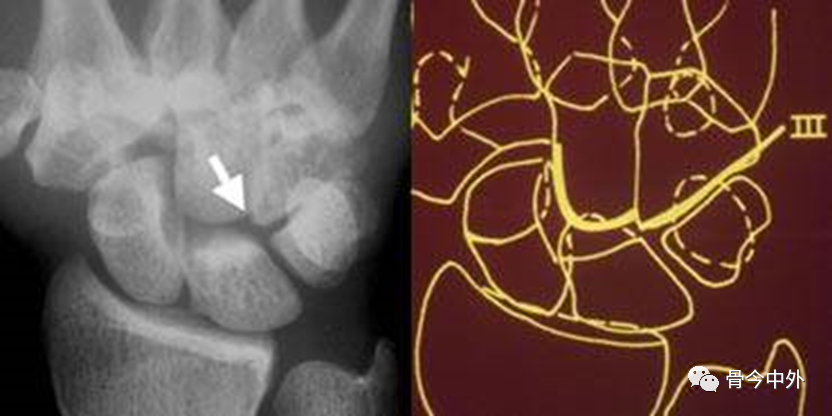

图19

弧线Ⅲ中断,上图显示头状骨-钩骨关节异常阶梯状改变。